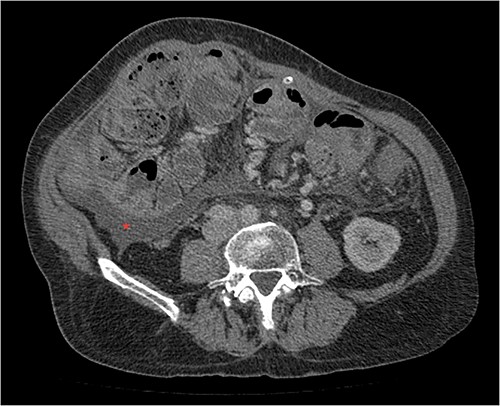

His clinical history and contrast-enhanced computed tomography (CT) findings (Figs 1–3) were compatible with EPS in Stage 4 (Table 2). Laboratory tests were non-specific, showing inflammation and malnutrition. He underwent nutritional support, corticosteroids and surgery. In surgery, fibrocollagenous membrane resection and enterolysis were done. Postoperative period was complicated by pneumonia treated with piperacillin+tazobactam and later bacterial peritonitis treated with ertapenem. The patient was discharged after 29 days with adequate nutrition and asymptomatic.

Portal phase transversal section image on CT showing loops wrapped in a membrane-like structure and thickened peritoneum.

Imaging exams, mainly CT are important to evaluate causes of bowel obstruction [4]. Dilated or non-dilated small intestine loops may be wrapped in a membrane-like structure, proximal bowel dilatation, thickened peritoneum with diffuse or local calcification, and loculated ascites are some of the findings on CT [1, 12]. Barium X-ray provides a clue to bowel encapsulation, showing clustered loops of the small intestine in the center of the abdomen, known as the cauliflower sign [4]. Ultrasound and magnetic resonance imaging may give a clue but are rarely used [1, 12].